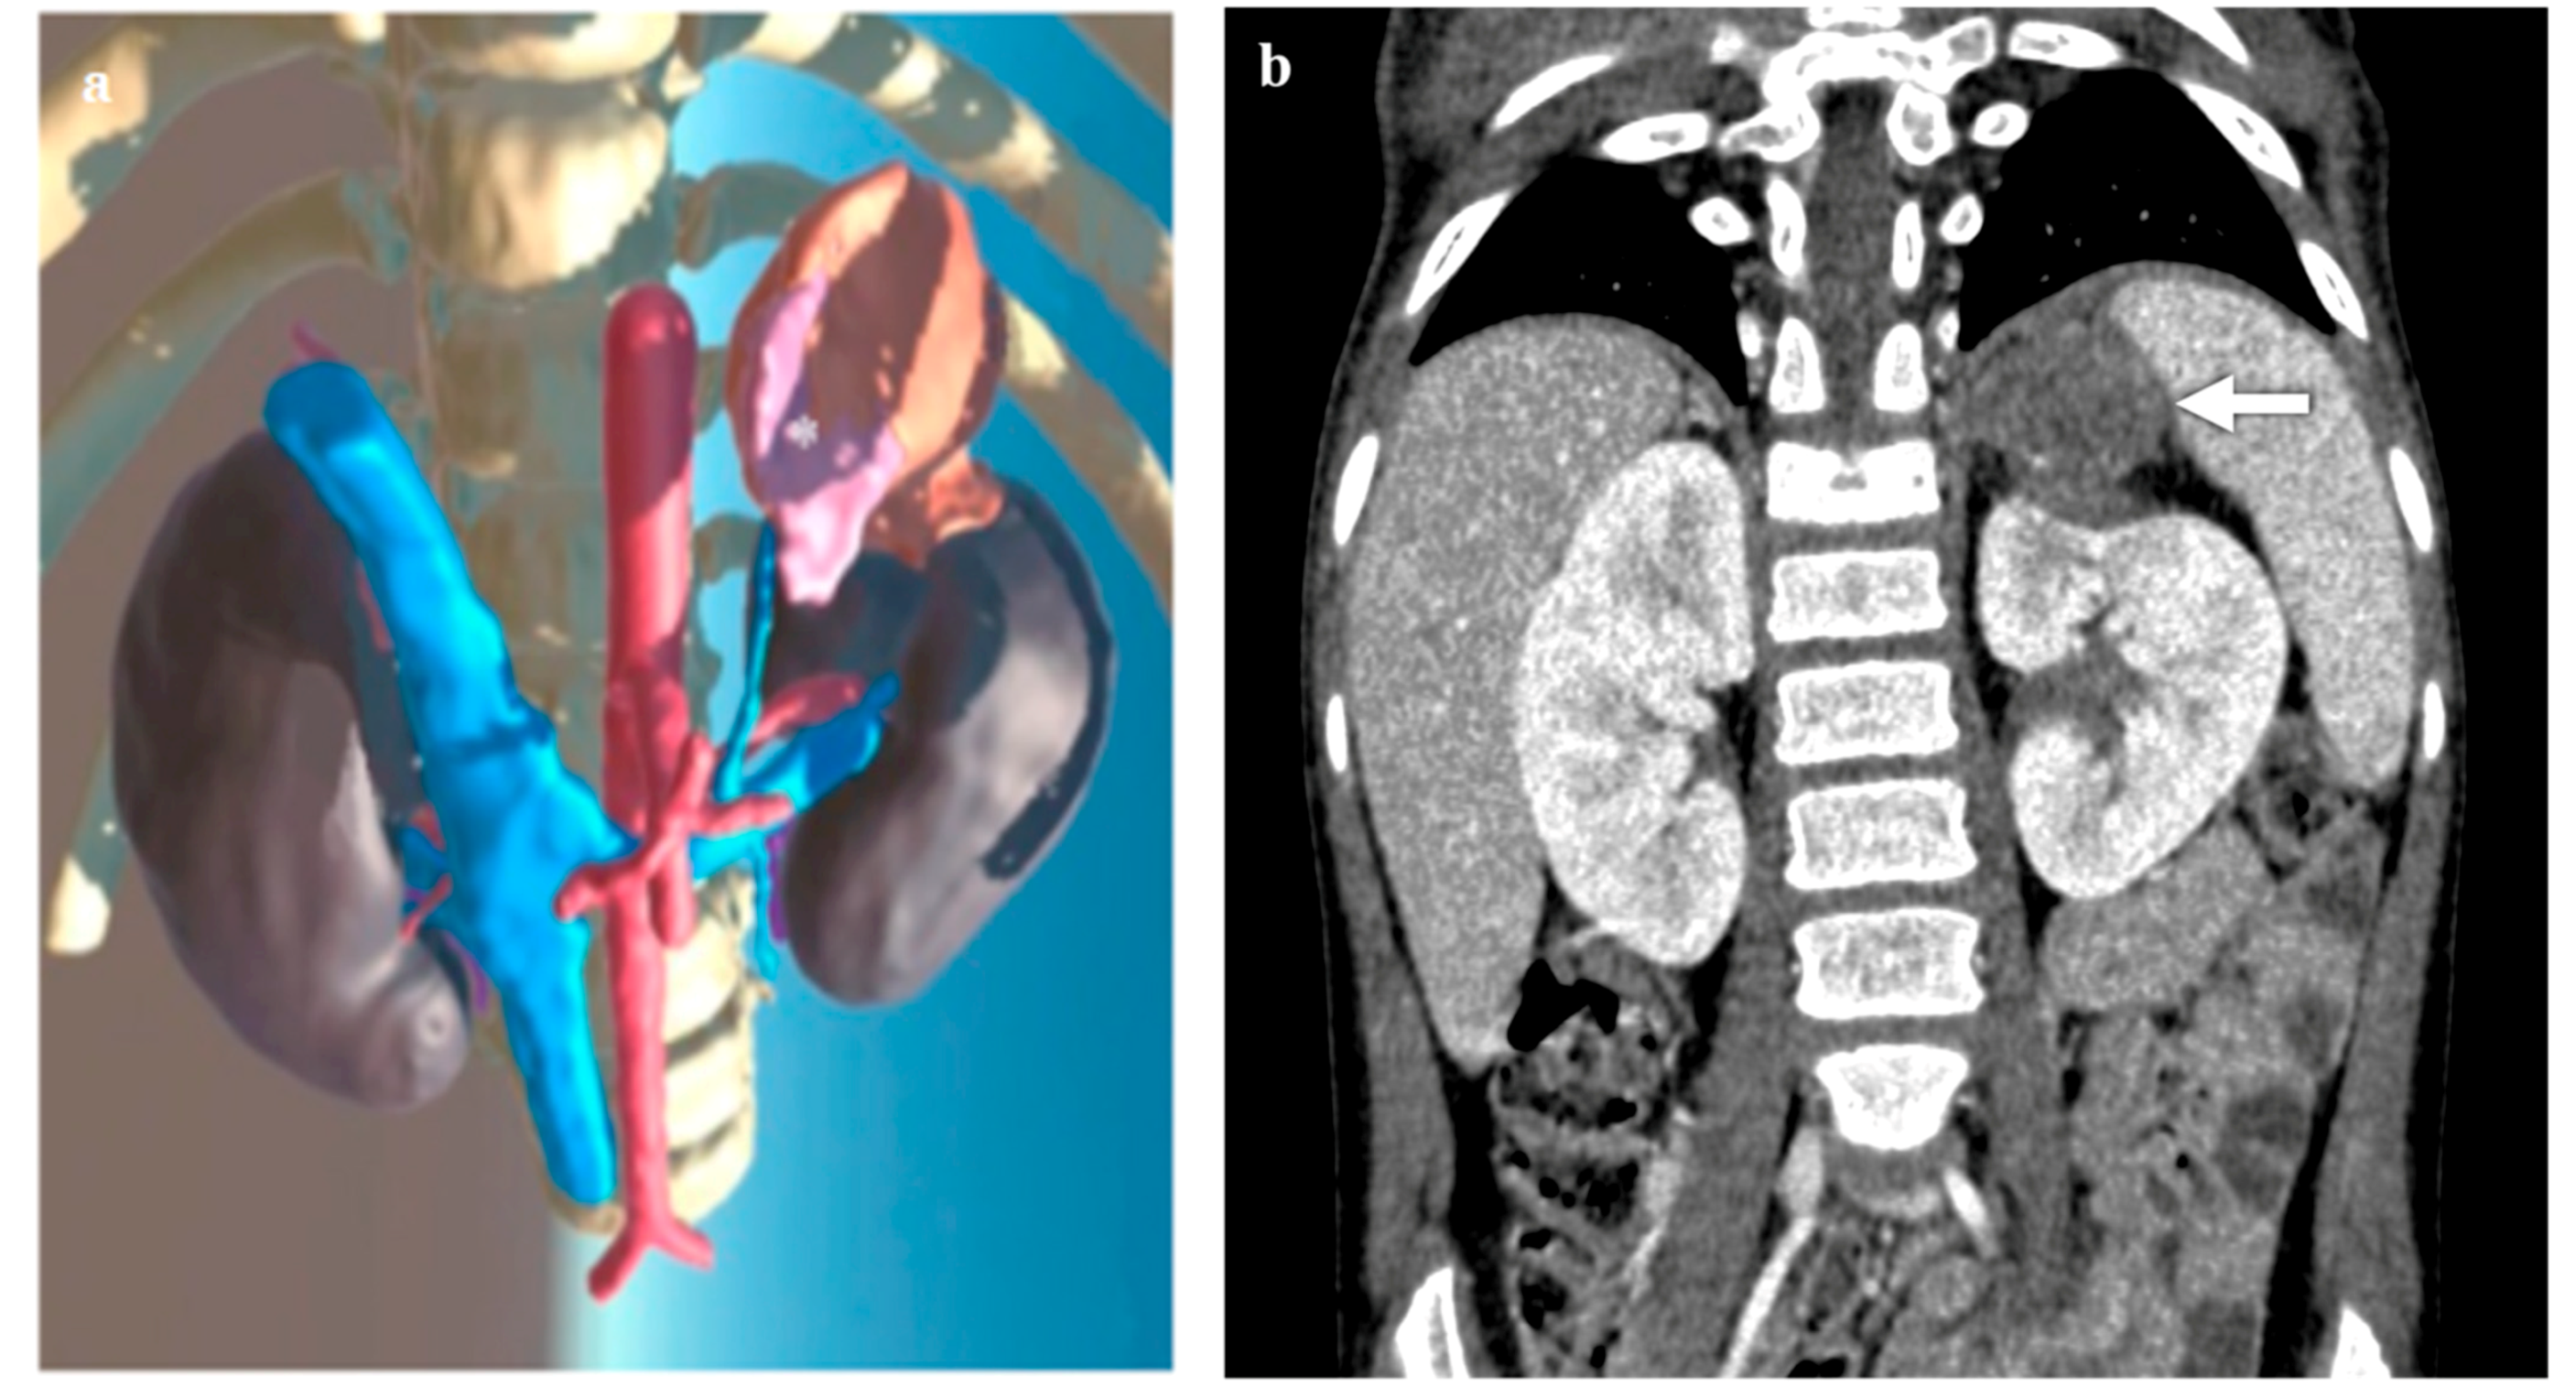

3.3. Kidney Lesions and Congenital Anomalies